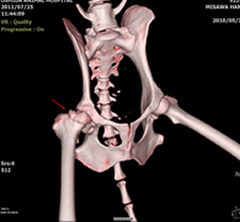

レッグ・ペルテス

無菌性大腿骨頭壊死症

大腿骨頭は変形壊死を起こし、慢性経過を辿ったため、骨盤側の変形も強かった症例です。